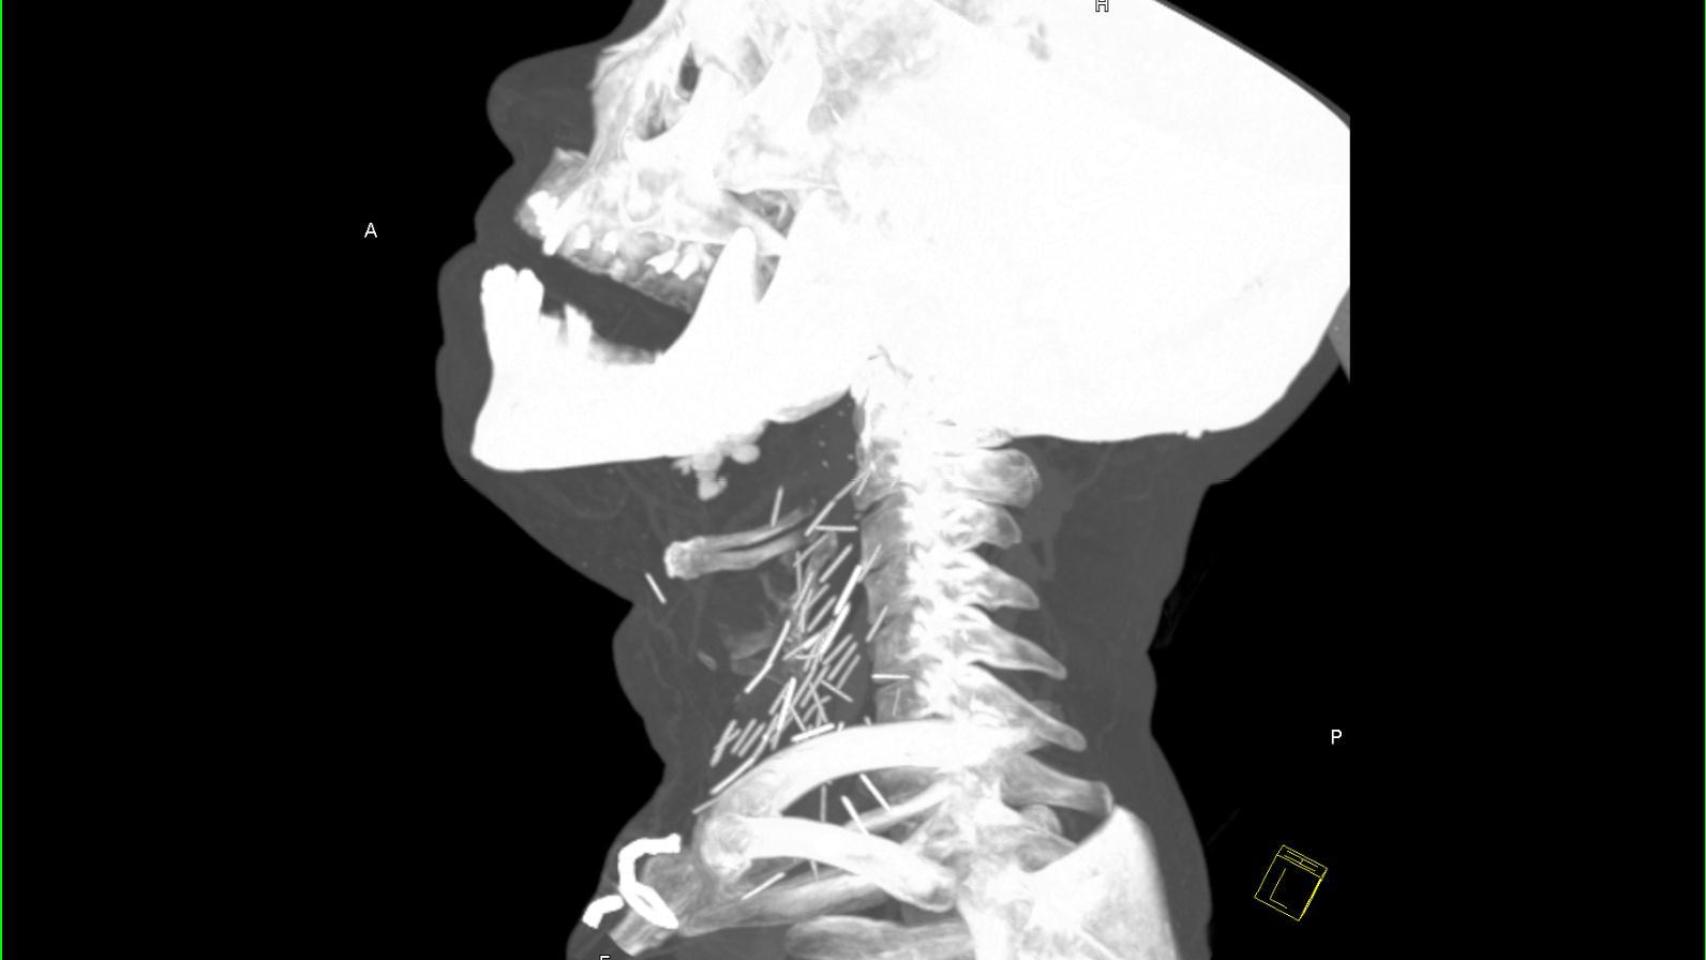

Aunque el caso data de hace 4 años, no fue hasta diciembre de 2015 cuando aparecieron las llamativas imágenes que anteceden a estas líneas en un subforo de Reddit -una de las comunidades de usuarios más grandes de internet-. En ellas se puede ver una radiografía del cuello de un adicto a la heroína repleta de agujas rotas.

Según la historia original de Reddit, la radiografía de este paciente apareció a raíz de su visita al servicio de urgencias de un hospital a causa de una neumonía. Tras examinar a este paciente con años de consumo de heroína a sus espaldas, se le hicieron una serie de pruebas y se comprobó que tenía el cuello lleno de agujas.

Si el consumo se prolonga durante muchos años, es común que las venas de los brazos, piernas, del pecho e incluso del abdomen queden inutilizadas. Es entonces cuando el cuello es su única alternativa y el motivo por el cuál este paciente tenía tal cantidad de agujas rotas en el suyo.